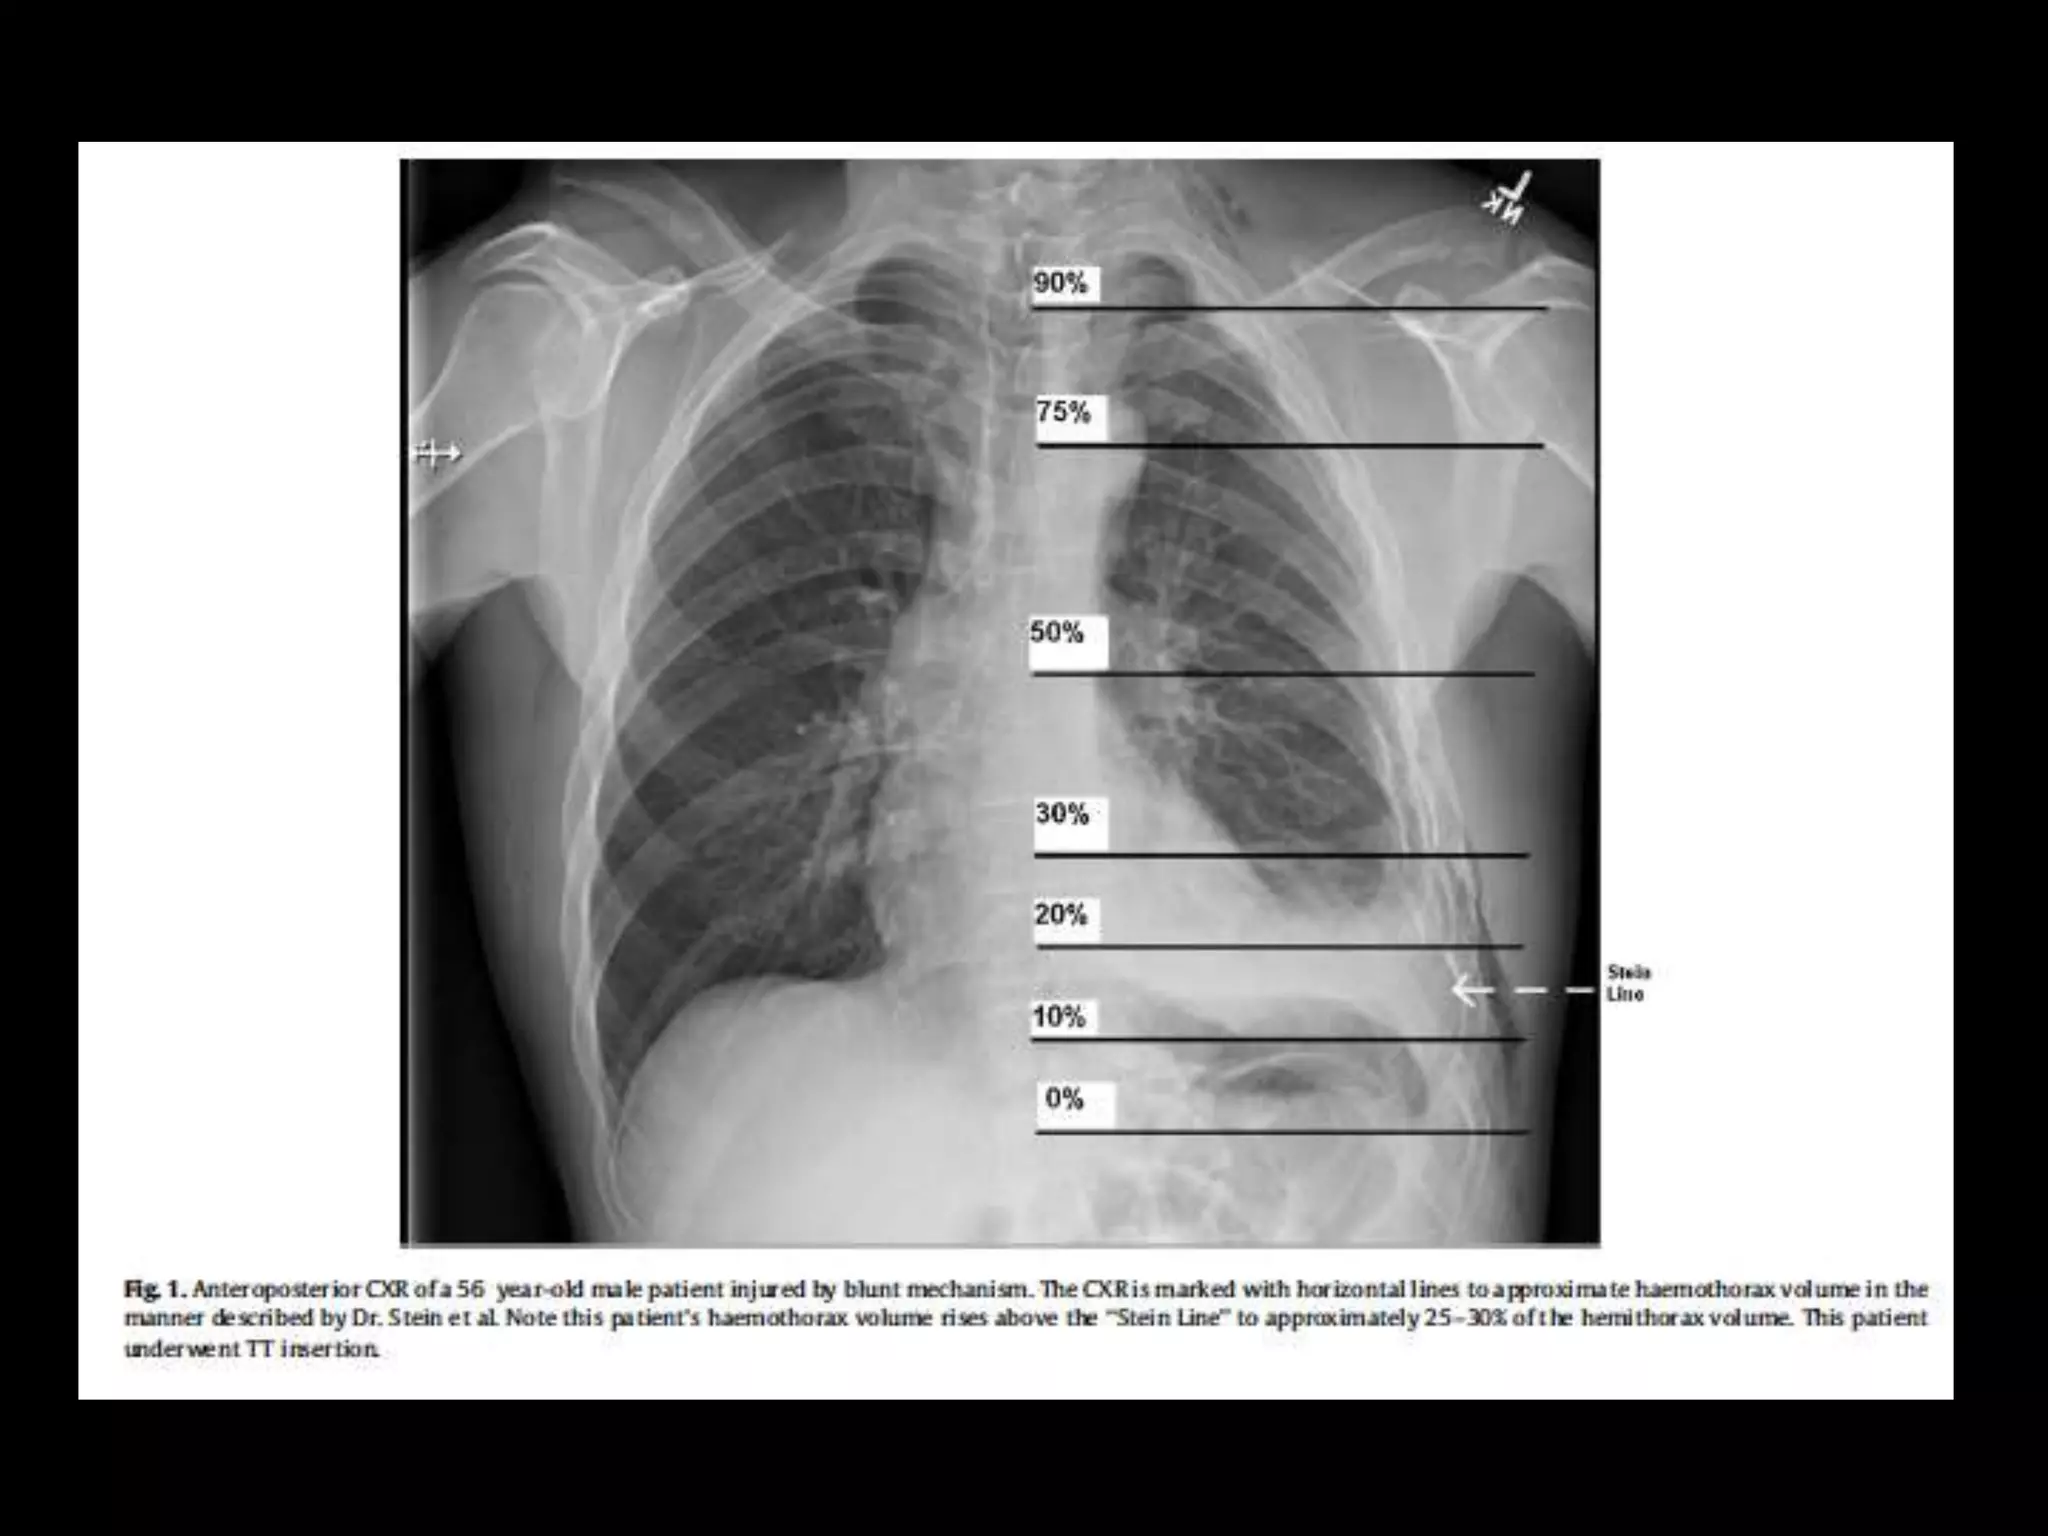

Haemothorax: To drain or not to drain?